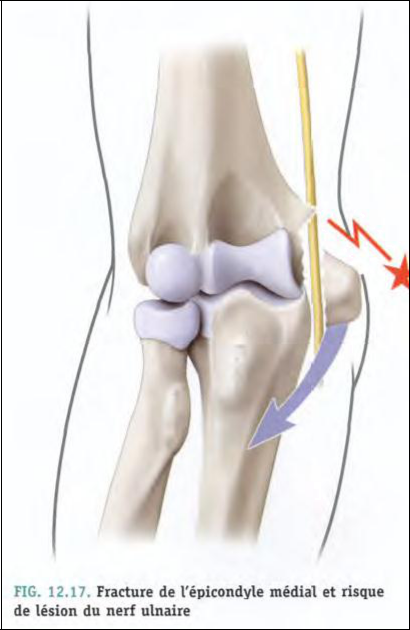

–il se situe dans la gouttière formée entre l’olécrane et l’épicondyle médial= gouttière épitrochléo-olécranienne (gouttière olécranienne)

L’épicondyle médial constitue le repère d’anesthésie du nerf ulnaire au coude(ou bloc du nerf ulnaire au coude)

Par section ou contusion tout au long de son trajet ; surtout au niveau du coude (Fracture de l’épicondyle médial)